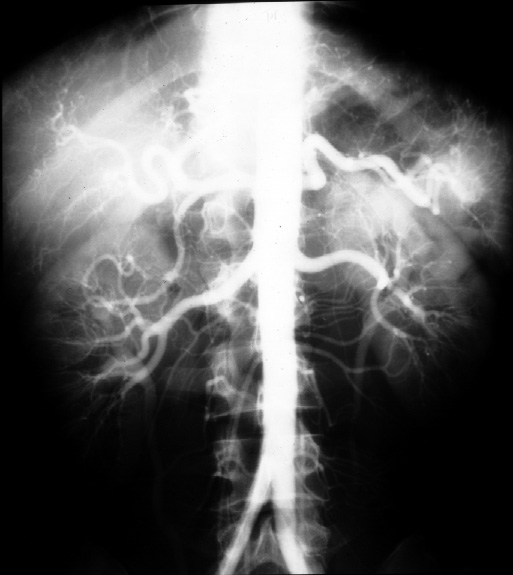

Radiology of Abdomen, Pelvis, and Perineum -- Normal Anatomy Arteriogram

(Frontal)

Identify the following arteries -- main hepatic, gastroduodenal, splenic,

hepatic proper, right and left renal, right and left hepatic